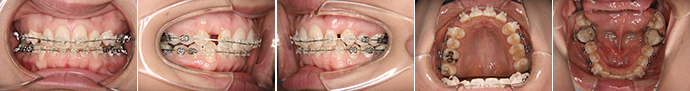

| 主訴 | 前歯が出ている |

| 年齢・性別 | 35歳 / 女性 |

| 治療方針 | 叢生も前歯の突出も大きいケース。小臼歯抜歯だけでは改善できないため、大臼歯の抜歯も行なった。 |

| 抜歯部位 | 上下顎左右小臼歯、左上第1大臼歯(計5本) |

| 使用装置 | マルチブラケット装置 |

| 治療期間 | 36か月 |

| リテーナー | 上顎インビジブル、フィックス、下顎インビジブル |

| 費用 | 885,000円(税別) |